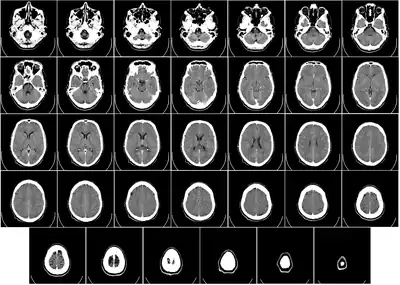

General images –